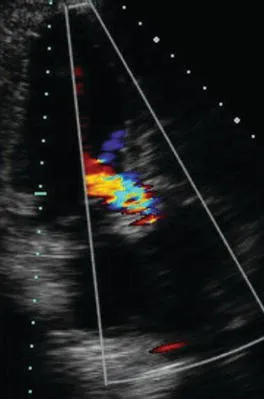

- Color Doppler: a color representation of blood flow velocities superimposed on a two-dimensional image (Figure 1.6).